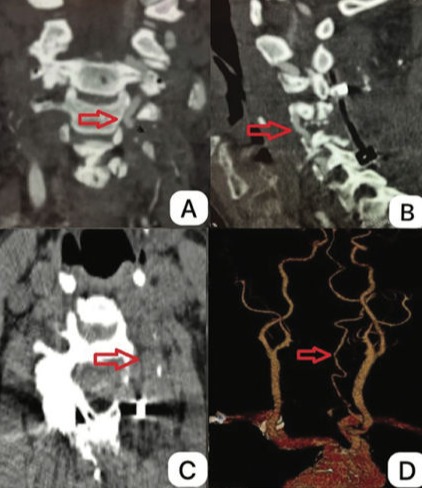

Vertebral Artery Stenosis Caused by Cervical Osteophyte: A Rare and Reversible Cause of Vertebrobasilar Insufficiency. Case Report.

A síndrome de Bow Hunter se manifesta quando a artéria vertebral é comprimida após a rotação da cabeça. A compressão sintomática com estenose da artéria vertebral devido a osteófitos cervicais é uma causa rara e ocorre devido a um processo degenerativo progressivo. Geralmente, a compressão se origina anteromedialmente do processo uncinado e é assintomática devido à competência da artéria vertebral contralateral.

No paciente descrito, a compressão se apresentou superomedialmente devido a osteófitos na faceta articular superior da vértebra C5, e a artéria vertebral contralateral estava obstruída. Uma avaliação cuidadosa com imagens, principalmente angiotomografia 3D pré-operatória, é necessária para determinar a abordagem mais benéfica para a descompressão. O tratamento de escolha para compressão sintomática induzida por espondilose cervical é a cirurgia de descompressão.